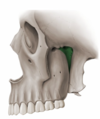

Label the articular eminence

X